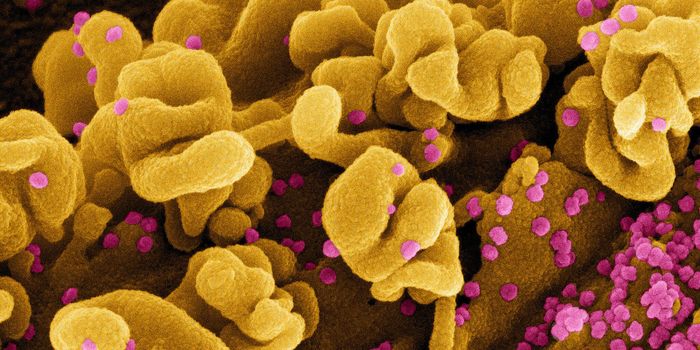

FEB 21, 2020Clinical & Molecular DXDiagnosing coronavirus is done through next-generation sequencing, real-time RT-PCR tests, cell culture, and electron mi ...